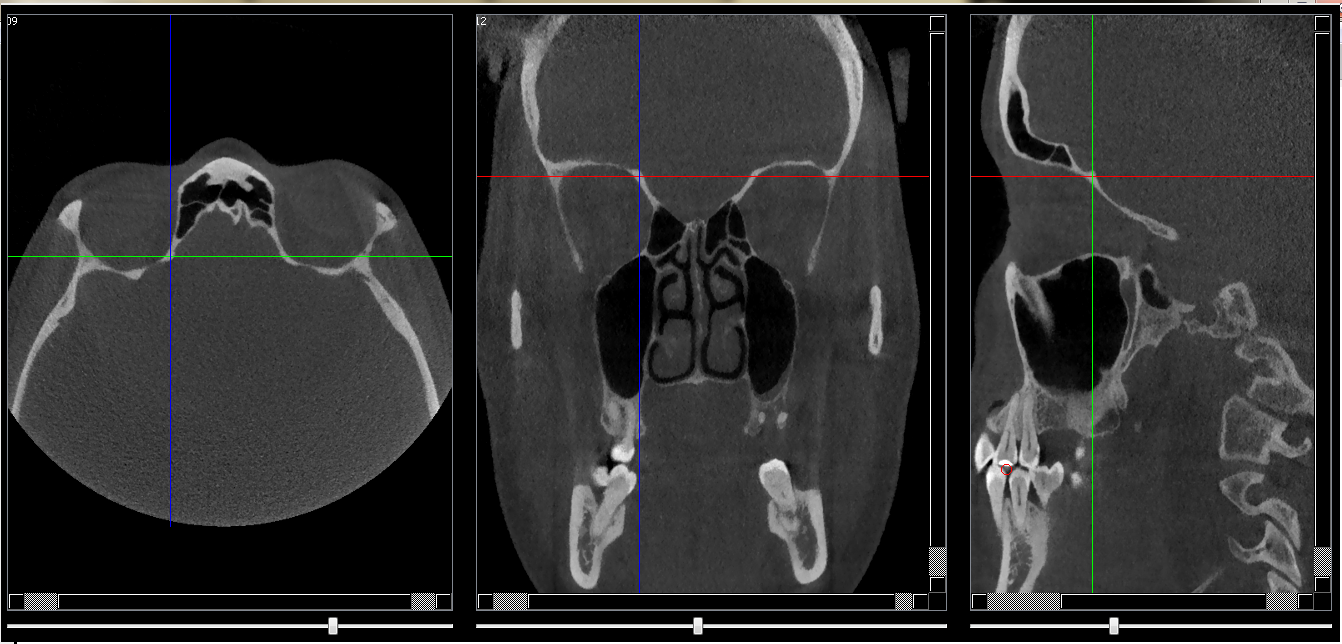

Structures osseuses

Partie horizontale de léthmoïde

Repères anatomiques

- Coupe transversale

- Début : Fissure orbitaire sup

- Fin : Plafond de l'orbite

- Coupe frontale

- Début : Sinus frontal

- Fin : Sinus sphénoide

- Coupe saggitale

- Début : Plafonde de l'orbite

- Fin : Paroi latérale de la fissure orbitaire sup